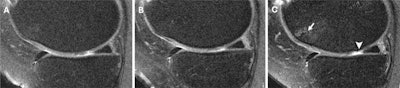

Knee MRI scans in a 58-year-old female participant who was administered a corticosteroid injection. Sagittal intermediate-weighted images obtained (A) two years before injection, (B) at the time of injection, and (C) two years after injection show a focus on the medial femoral cartilage and trochlea. (C) The postinjection scan shows a new full-thickness cartilage lesion in the medial femoral cartilage (arrowhead), whereas images from the preinjection time points show a well-preserved medial femoral cartilage (A, B). The postinjection scan (C) also shows the development of a new full-thickness cartilage lesion in the medial femoral cartilage and a new bone marrow lesion in the trochlea (arrow), both of which were absent in the preinjection scans. These findings suggest structural deterioration following the corticosteroid injection.RSNA